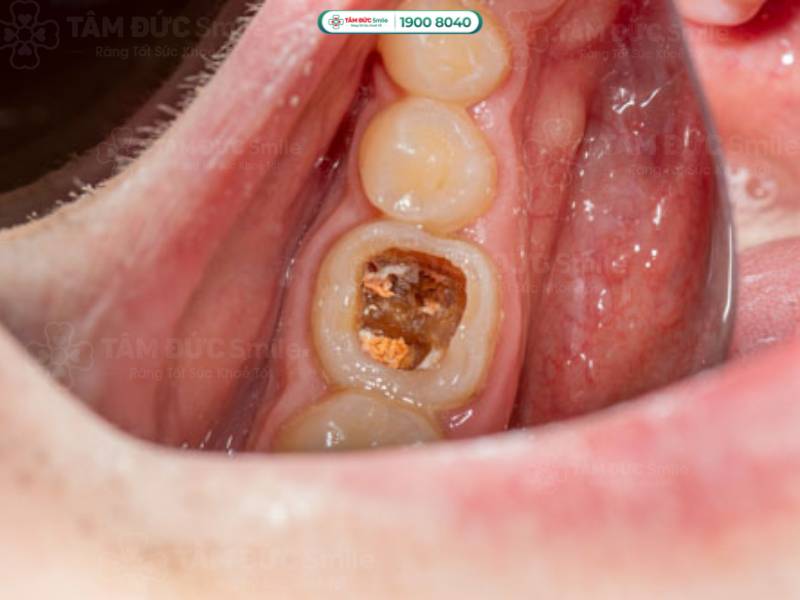

1.2.4. Sâu răng độ 4 là gì?

Cấp độ 4 là giai đoạn sâu răng nghiêm trọng nhất, nếu không can thiệp kịp thời sẽ tạo điều kiện cho vi khuẩn lan đến vùng nha chu. Ở giai đoạn này, các lỗ sâu răng trở nên lớn hơn, răng có thể bị mẻ hoặc vỡ thân răng. Điều này dẫn đến các triệu chứng như sưng mặt, tiêu xương, rụng răng, ảnh hưởng đến các răng lân cận…

Sâu răng độ 4 gây mẻ hoặc vỡ thân răng